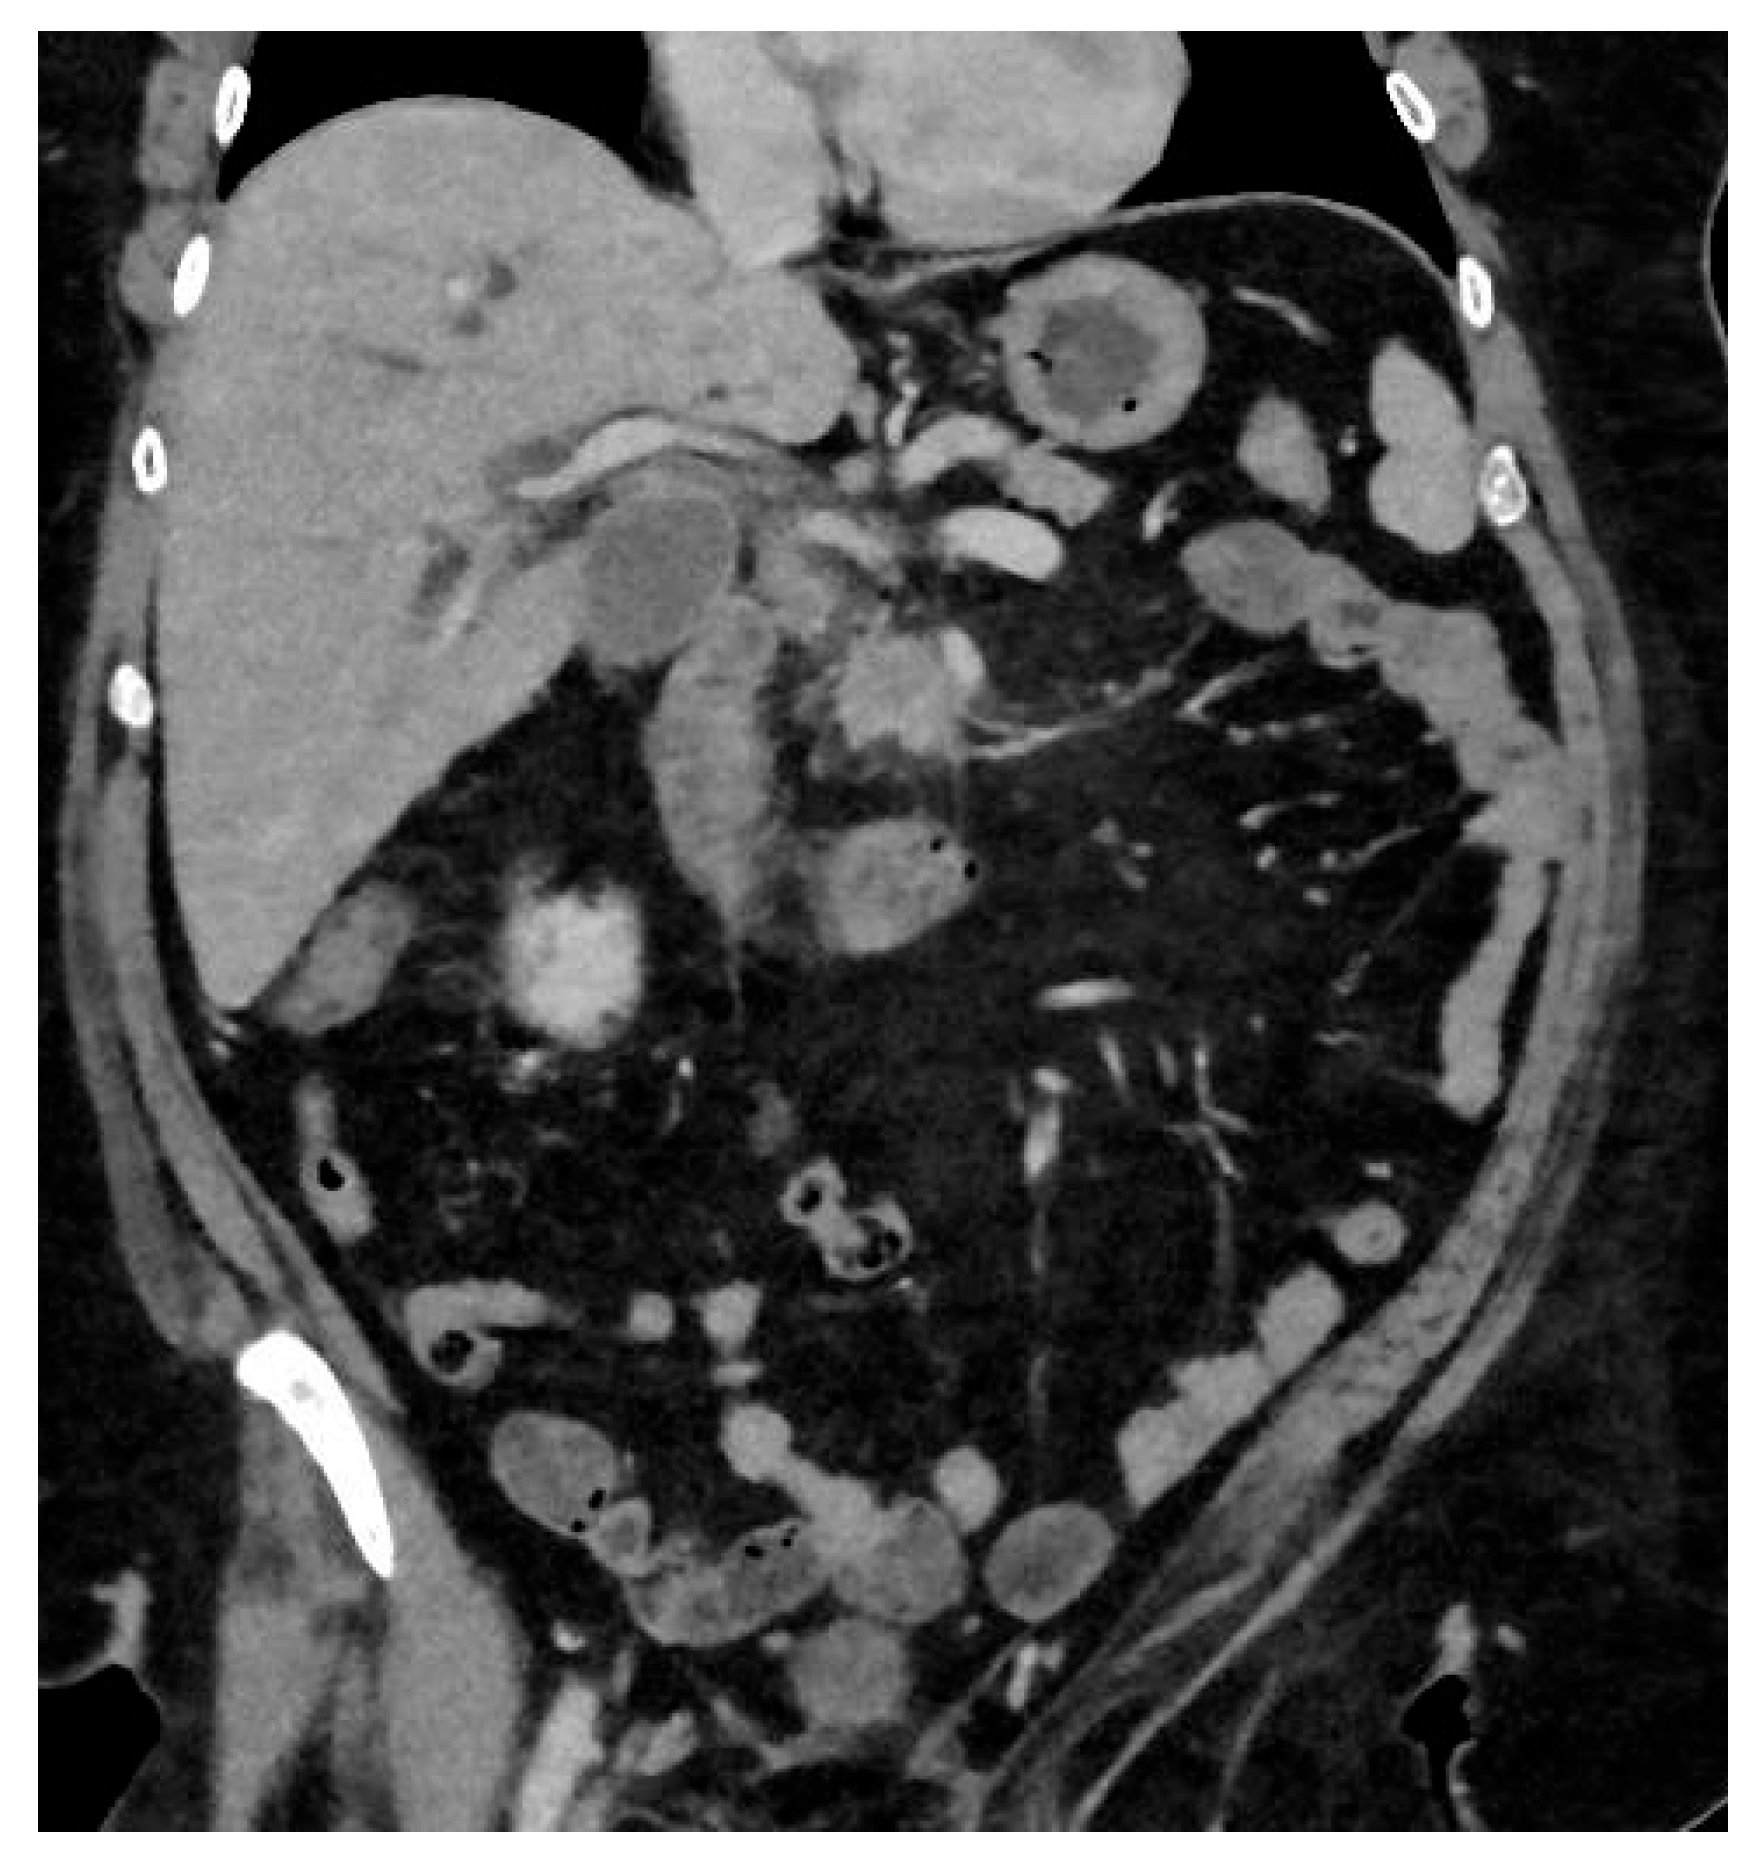

Pancreatic ductal adenocarcinoma (PDAC) is an aggressive form of cancer that carries a poor prognosis. PDAC usually occurs in the head of the pancreas. It is estimated that between 80 and 85% of PDAC lesions are advanced and irresectable, or non-curable, at presentation. This is mainly because the symptoms that patients experience can be vague and non-specific, like abdominal pain, and the symptoms can be challenging to diagnose, leading to delays in diagnosis. See Figure 2.

Figure 2. Hypodense lesion in the head of the pancreas, biopsy adenocarcinoma treated with Whipple.